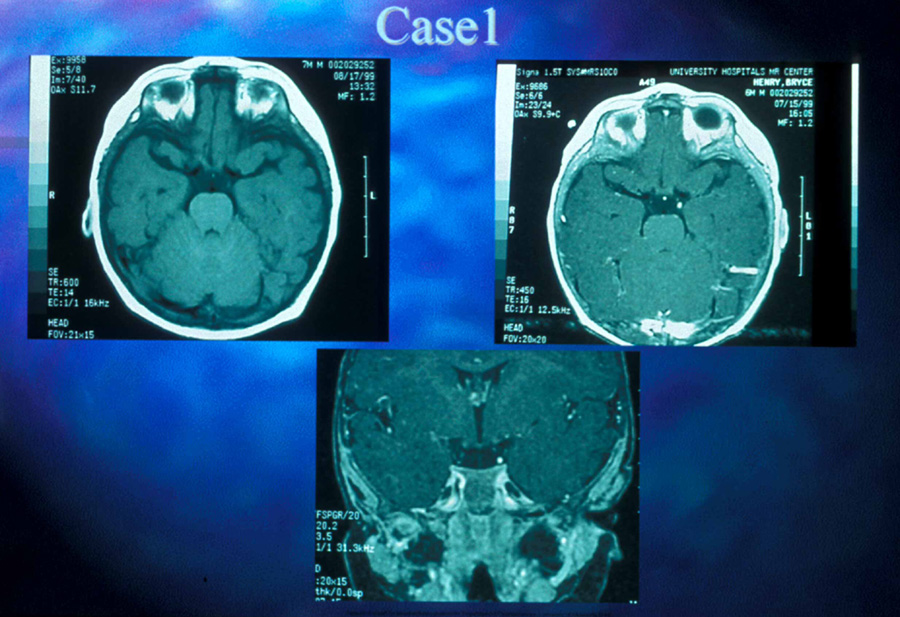

Fig. 10. Six-year-old boy with Wolfram (DIDMOAD) syndrome. Note symmetric temporal pallor of both optic discs. Vision was 20/60 in each eye.

Anterior visual pathway gliomas account for the majority of intrinsic optic nerve tumors in childhood (Figs. 11, 12). Although they are true neoplasms, malignant features are extraordinarily rare in the pediatric population (see Chapter 5). Dutton58 provided a thorough review of this subject. When the glioma is initially confined to the optic nerve alone, the mortality rate is 5%. However, when the hypothalamus is involved, survival is less than 50% in some series. With a typically indolent course, these tumors generally can be managed conservatively, especially when confined to the optic nerve. Hoffman et al59 reviewed 62 cases of optic pathway/hypothalamic gliomas over a 14-year period, with 48 of these exhibiting relative stability with only visual defects: six patients had significant neurologic abnormalities, and eight died. Gayre et al60 reported a series of 42 patients with optic gliomas seen over 28 years at a single institution. Two-thirds were female, and slightly over half had neurofibromatosis type I (NF-1). Presenting signs and chiasmal involvement were similar in both NF (+) and NF (–) groups, the latter usually occurring within the first year after diagnosis. Regardless of treatment, the eye with better vision tended to remain stable over the long-term (and vision in the poorer eye often declined). Spontaneous regression of optic gliomas with visual improvement also has been reported.61,62

Fig. 11. Magnetic resonance imaging scans of optic gliomata. A. Marked enlargement of optic chiasm on coronal image. B. T1-weighted, gadolinium-enhanced image showing enlargement and marked enhancement of the right optic nerve and chiasm.